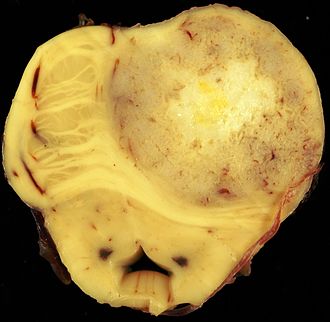

| Glioblastoma (WHO grade IV) | glial processes (esp. on smear), nuclear atypia (typical size var. ~3x, irreg. nuc. membrane, hyperchromasia), no Rosenthal fibres in the core of the lesion †, microvascular proliferation or necrosis | often enhancing (suggests high grade), usu. supratentorial, usu. white matter | usu. old, occ. young | very common, esp. glioblastoma | IDH-1+/-, GFAP+ | |

| Metastasis | sharp interface with brain, often glandular, +/-nucleoli, no glial processes | often cerebellular, well-circumscribed | usu. old | often suspected to have metastatic disease | TTF-1, CK7, CK20, BRST-2 |

Brain metastasis